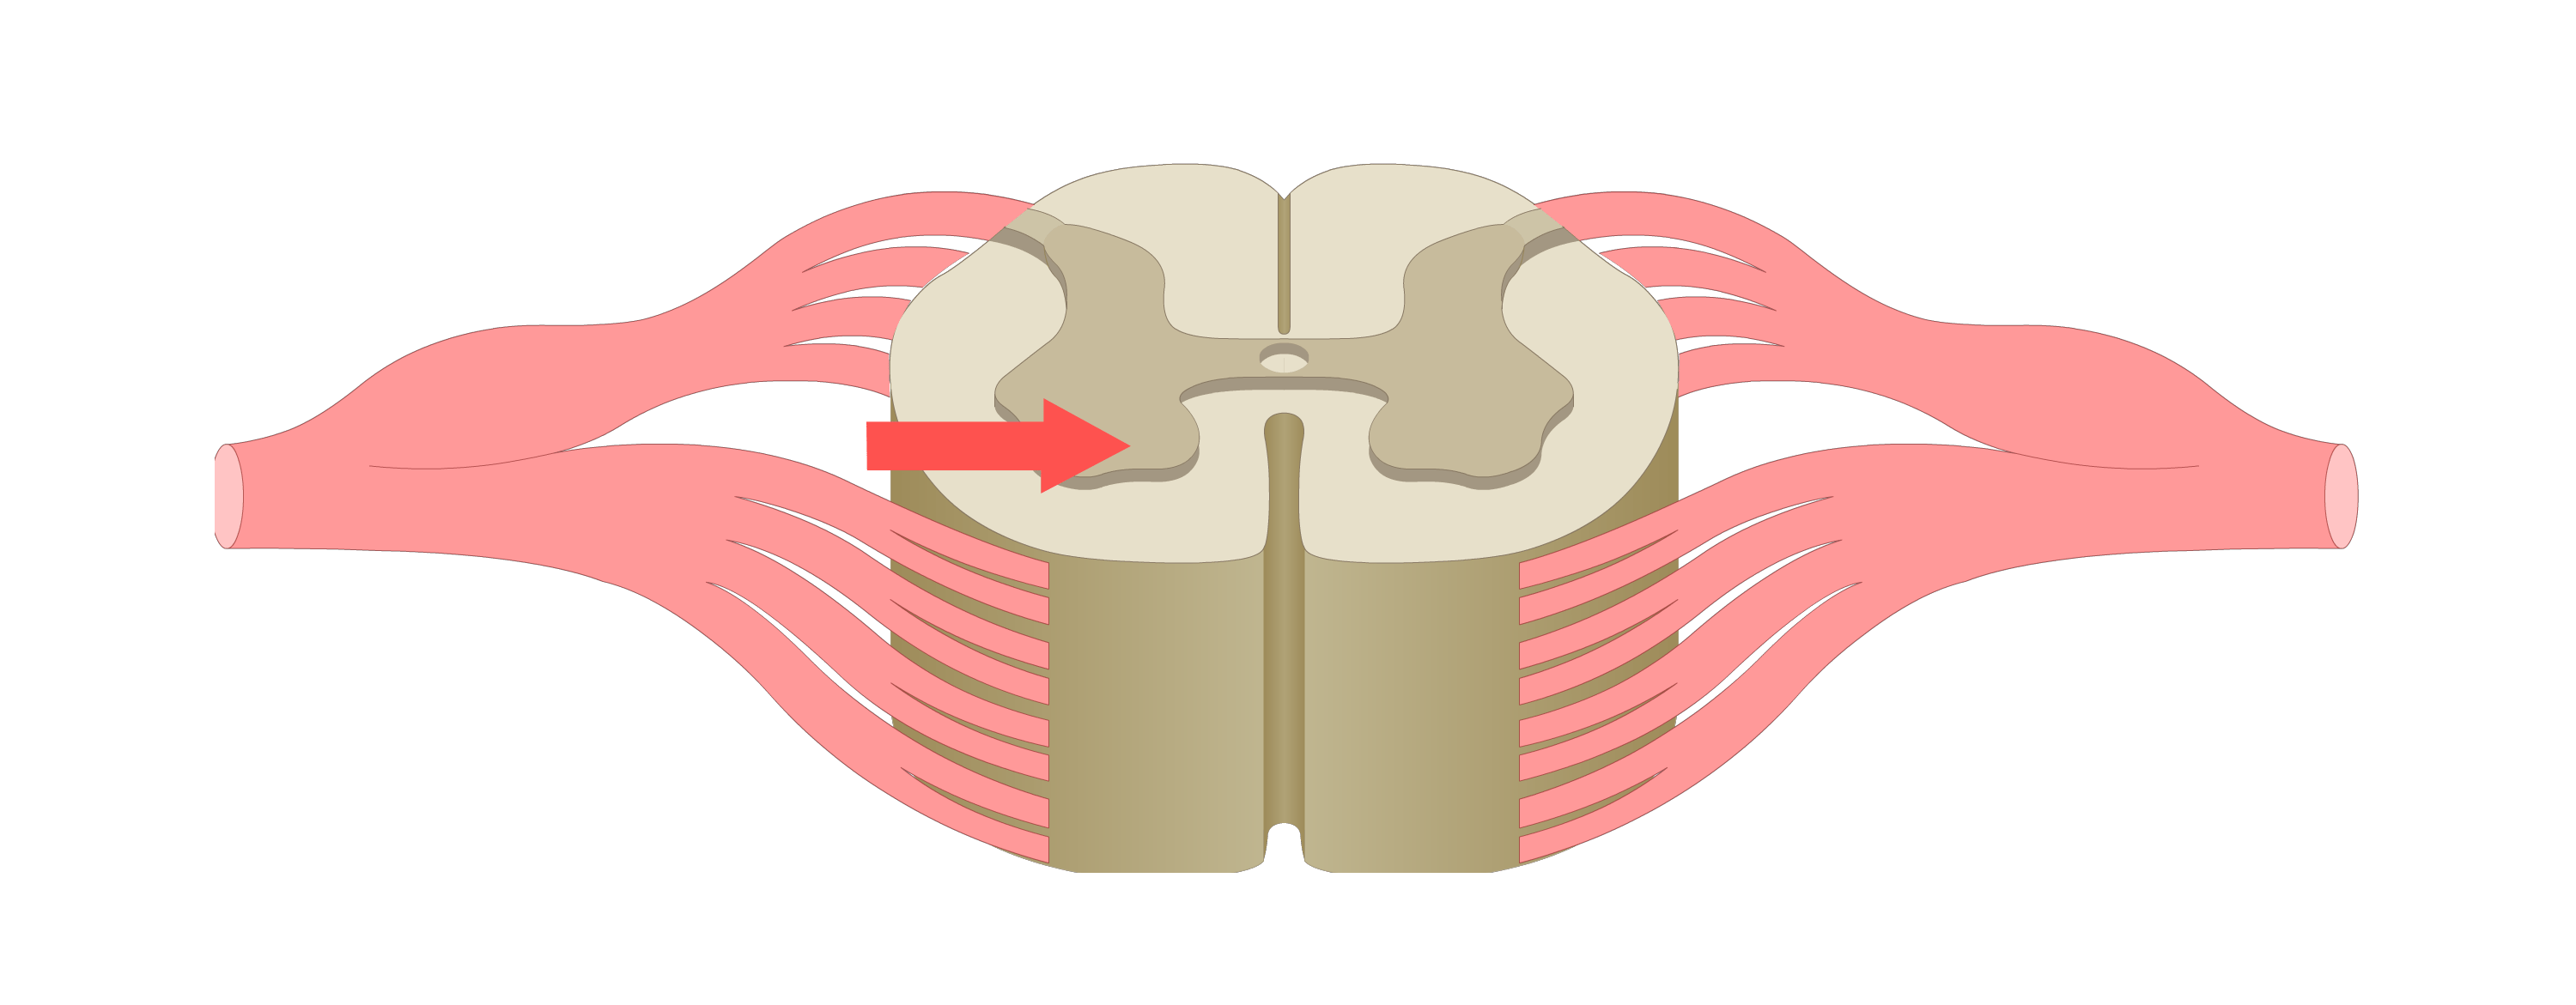

motor tracts

sensory tracts

dorsal root ganglion

dorsal horn

lateral horn

ventral horn

dorsal funiculus

lateral funiculus

ventral funiculus

central canal

ventral median fissure

dorsal median sulcus

afferent neuron

carries sensory action potential from receptor to CNS

efferent neuron

carries motor action potentials from integration center to effector organ

control/integration center

single/multiple synapses bw sensory & motor neurons; always in CNS